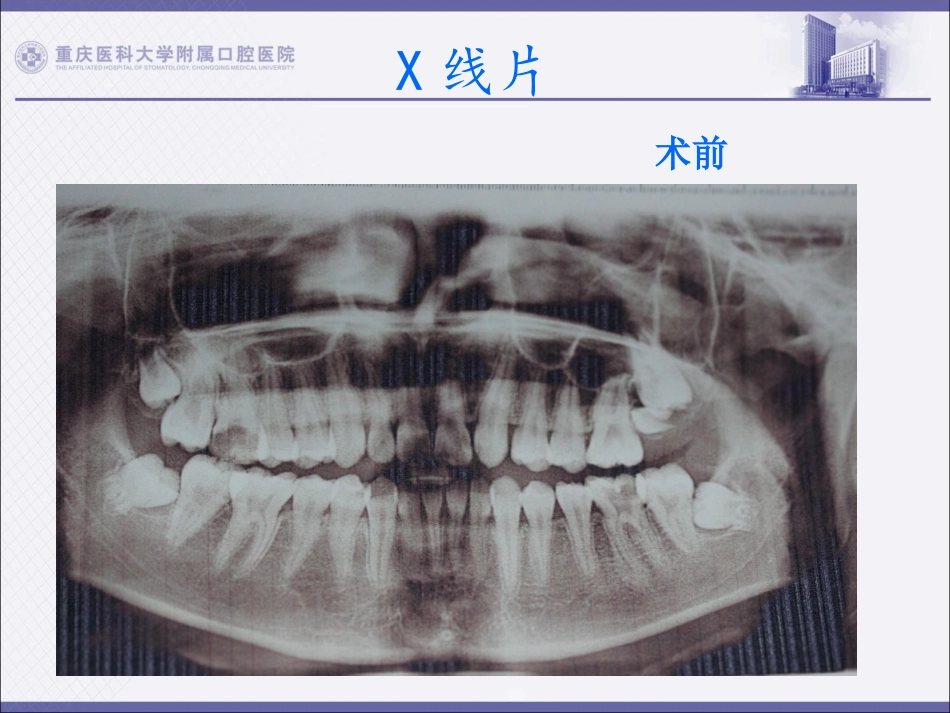

2015年5月牙体牙髓病例1(牙龈增生及牙髓息肉伴4根管病例)姓名:马宇杰就诊时间:2015年1月29日病例摘要姓名:马某男17岁主诉:左右上下后牙冷热刺激疼痛5-7日现病史:16深龋到髓腔,见息肉于髓腔内,探-,冷+-++松-叩-。36深龋穿髓,探++,松-叩-冷+-++,舌侧牙龈增生覆盖与髓腔表面。既往史:2014年10月左侧颞叶基地节区脑出血破入脑室,行开颅手术诊断:16牙髓息肉及牙髓炎36牙髓炎伴牙龈瘤处理:16,36试行根管治疗+冠修复。(告知患者16,36条件差,如治疗过程中,发现穿髓底过大,建议拔除,患者接受。)X线片术前x线片术前X线片36术前x线片36术中高频电刀切除增生牙龈,修整牙龈外形。常规开髓揭盖,拔髓,机扩4根管。x线片36术中封药2周后无疼痛及分泌物,热牙胶根充x线片36术后x线片16术前x线片16术中x线片16术后36x线片对比术前术中术后16x线片对比术前术中术后谢谢大家